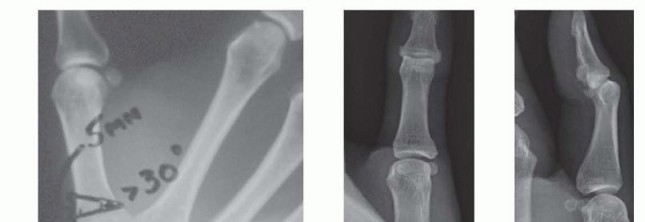

A dorsal approach is used and subperiosteal exposure of the base of the metacarpal is provided.The osteotomy is made 1 cm distal to the base and is 5 mm wide, so the incision should extend 4 cm distal to the base.The base of the wedge is therefore 5 mm wide and is dorsal. Its apex is palmar.P.1058

TECH FIG 1 • A. Radiograph showing planned osteotomy. B,C. AP and lateral postoperative thumb radiographs. Use a microsagittal saw to score the metacarpal 1 cm distal to its base transversely, but do not make a complete cut through the volar cortex.Leave a new saw blade in that partial osteotomy site and use a second blade about 5 mm distal to the first cut at an angle of 30 degrees so that the two blades intersect at the volar cortex.Remove the wedge of bone, extend the distal metacarpal and compress it against the proximal fragment, and place one 11 × 8 staple (OSStaple, BioMedical Enterprises, Inc., San Antonio, TX).Typically, I maintain the reduced position of the metacarpal while my assistant predrills and then places the staple (TECH FIG 1B,C).Perform a layered closure of the periosteum and skin and place an overlying thumb spica splint.1. Extension Osteotomy with Kirschner Wire and Tension Band FixationThe technique is as described for staple fixation except for the use of Kirschner wires.Use a microsagittal saw to score the metacarpal 1 cm distal to its base transversely, but do not make a complete cut through the volar cortex.Leave a new saw blade in that partial osteotomy site and use a second blade about 5 mm distal to the first cut at an angle of 30 degrees so that the two blades intersect at the volar cortex.Remove the wedge of bone and use a 0.045-inch Kirschner wire to place a transverse hole on either side of the osteotomy.Pass a 22-gauge wire radial to ulnar and ulnar to radial.Place a 0.045-inch Kirschner wire retrograde through the distal osteotomy site, exiting out the ulnar aspect of the thumb, and compress the osteotomy by extending the distal metacarpal.With an assistant maintaining compression, tighten the wire, cut it, and bend it beneath the thenar musculature. Then advance the Kirschner wire anterograde.Cut the Kirschner wire external to the skin to facilitate removal, and repair the periosteal origin of the thenar musculature with absorbable suture.P.1059